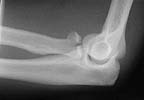

Lateral

I did an open reduction and Herbert screw fixation. On table before opening the # there was a block to pronation and supination to the same extent as noticed preop. (Post op films:radial head2)

Postop lateral